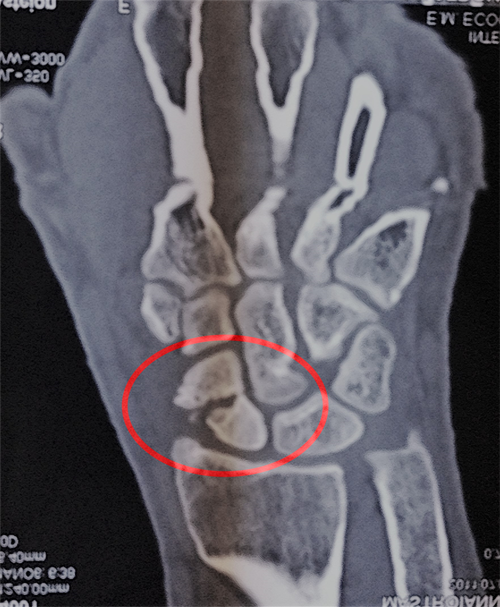

– Tomografia Computerizzata (TAC): fornisce immagini dettagliate, specialmente nei casi di fratture scomposte.

Esame rx di pseudoartrosi scafoide